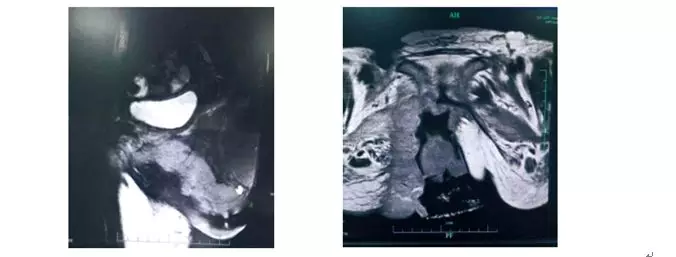

侵犯耻骨,化疗2 个疗程后病灶无缩小,放疗科医生拒绝放疗,家属要求手术。病灶见图。

患者外阴癌侵犯耻骨及CT 影像

病灶包绕尿道,与阴道前壁分界不清,阴道结构紊乱,与直肠分界欠清,直肠壁局部稍增厚。病灶包绕部分双侧耻骨联合、右侧耻骨下支及右侧坐骨,增强后呈明显强化;双侧腹股沟、髂血管旁及盆腔内见多发肿大淋巴结影。会阴部、双侧腹股沟皮肤局部见多发破溃,增强后呈明显强化。子宫及双侧附件区未见明显异常信号灶。膀胱充盈可,膀胱腔内未见明显异常信号灶。